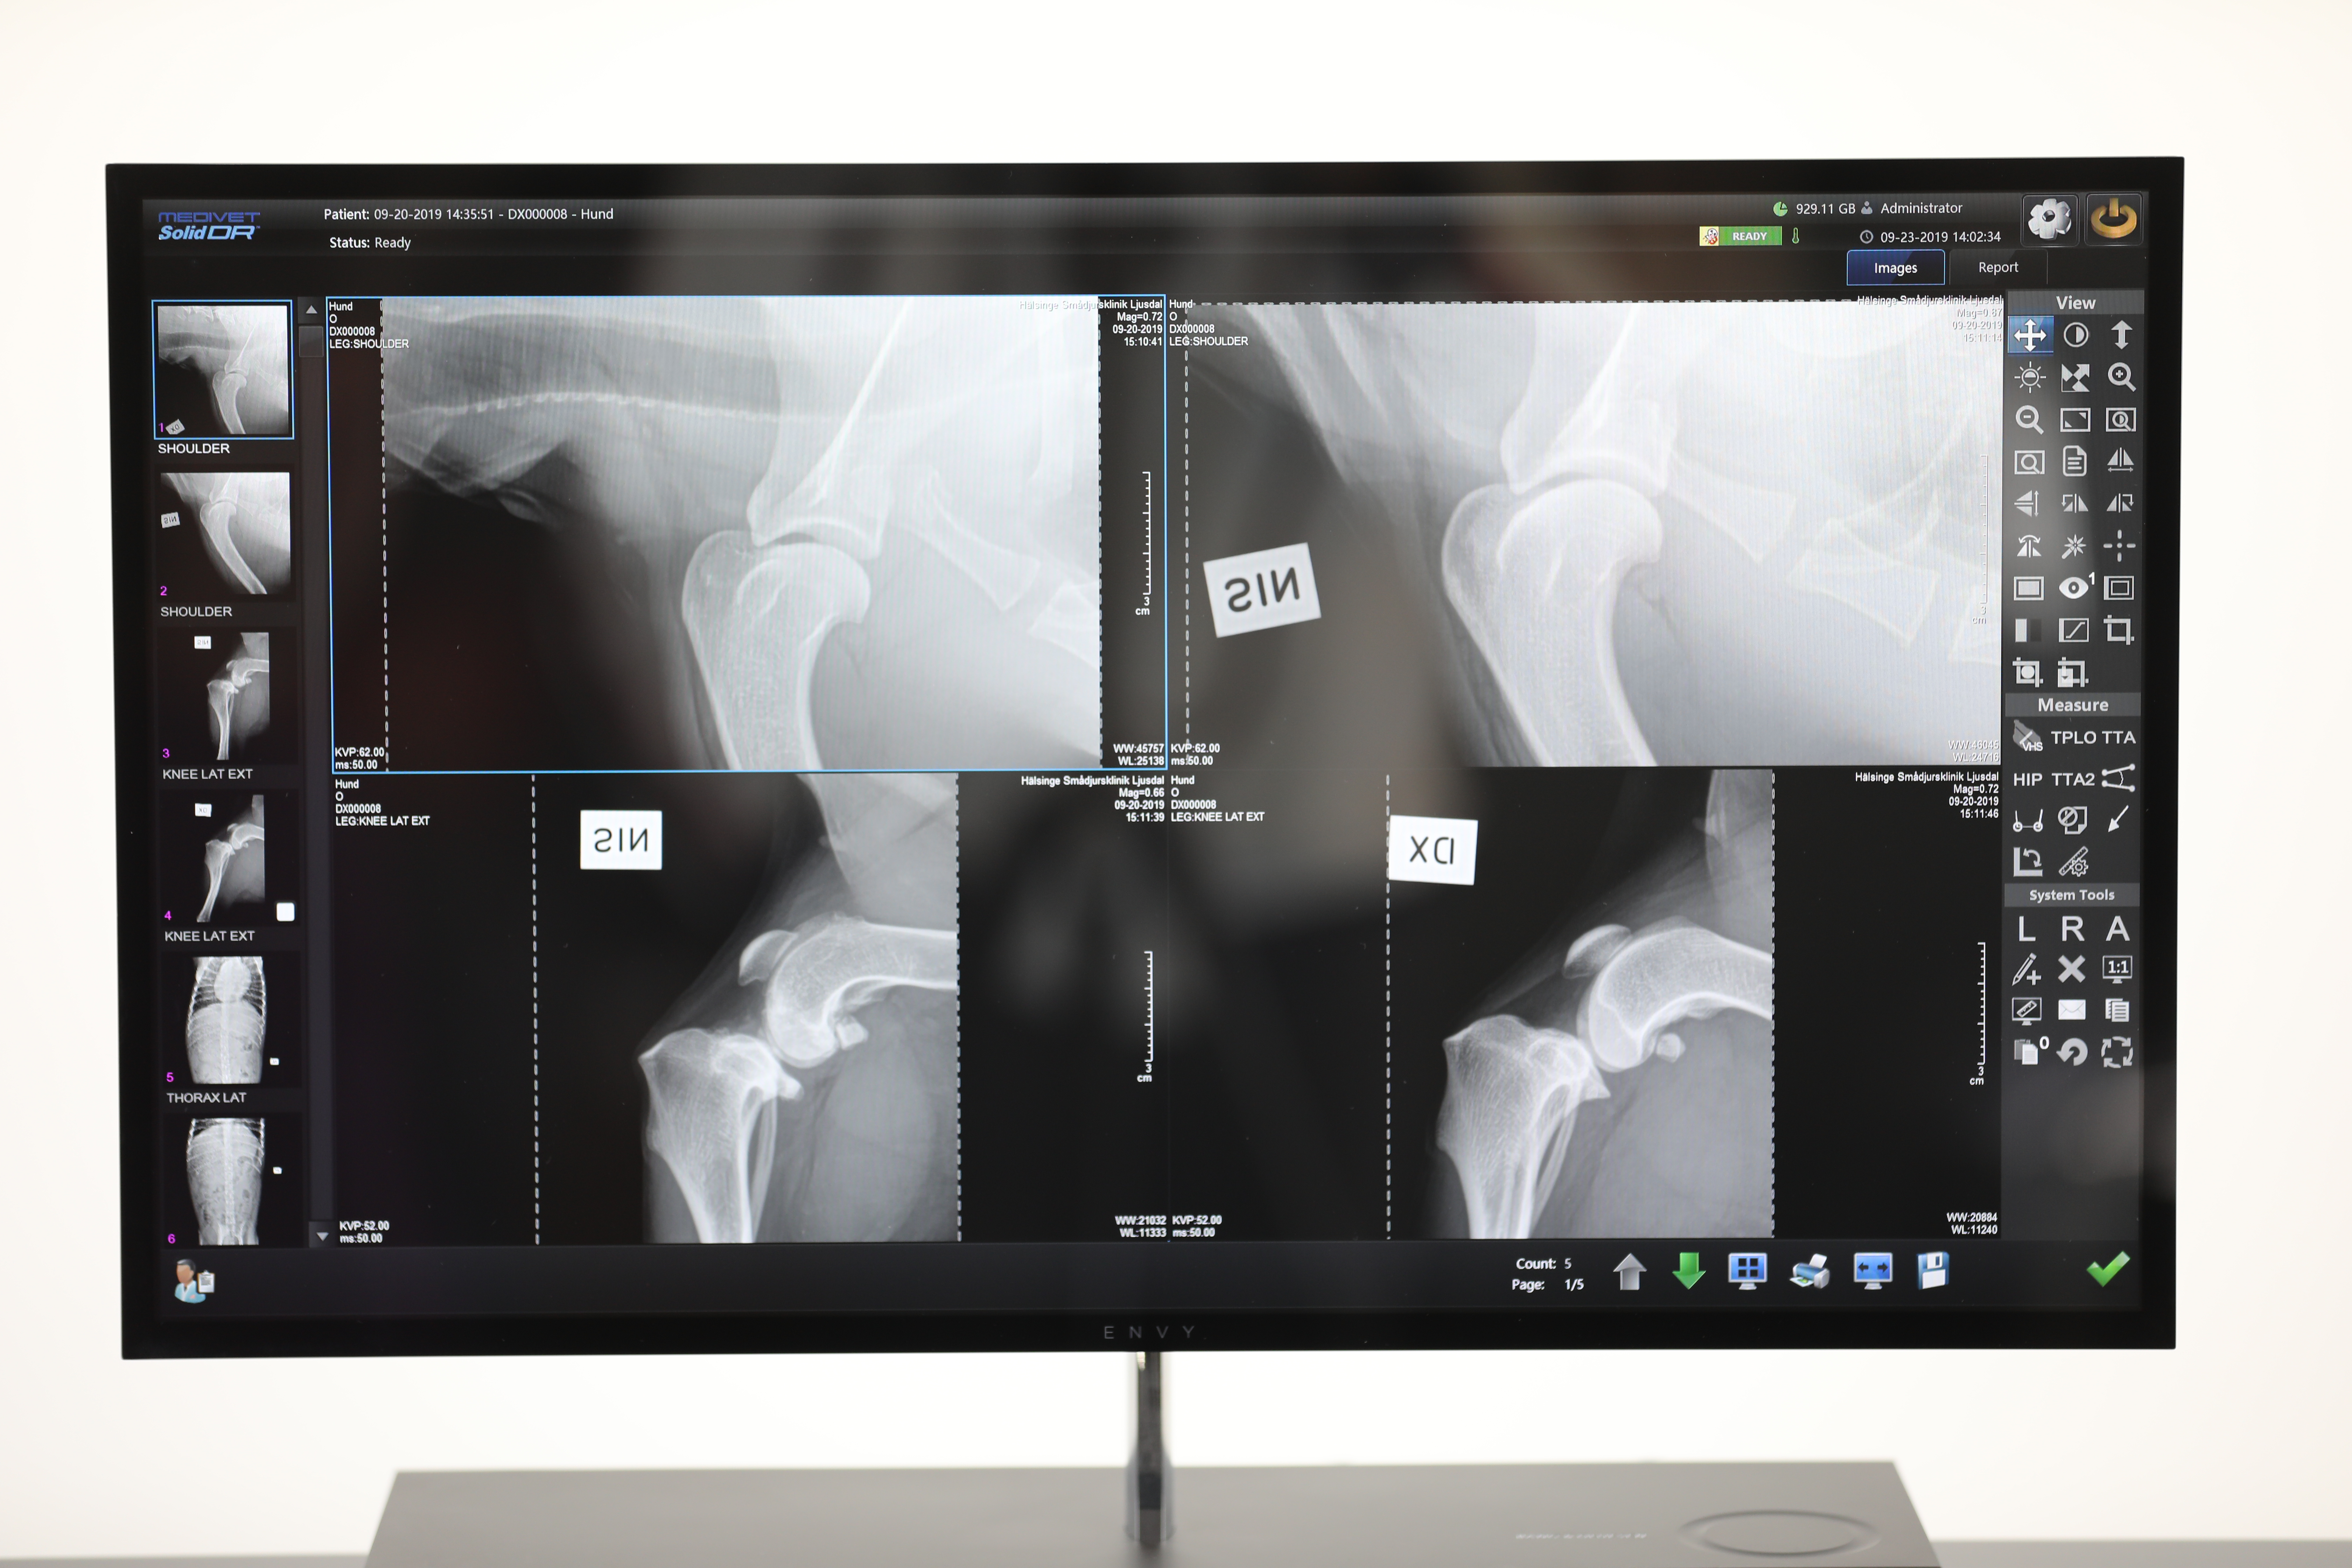

SolidDR CX

SolidDR serien har varit populär sedan vi introducerade systemen år 2018. Med över 100 system levererade finns det många referenser och nöjda kunder.

Systemet är en Medivet-byggd lösning där vi själva har valt komponenter och optimerat både applikation, funktion samt bildresultat.

SolidDR har uppdaterats kontinuerligt genom åren med sin sista version 2023 och då i CX utförande.

SolidDR konceptet är utvecklat genom samarbete med slutanvändare där vi fastställde vilka egenskaper vi ville uppnå med systemet.